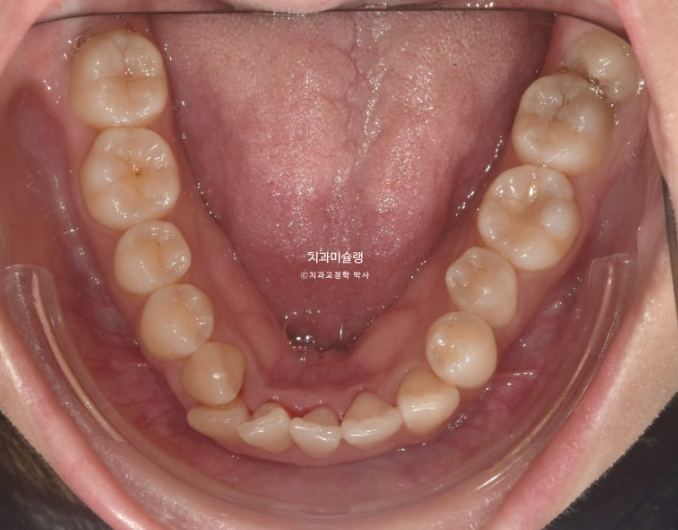

덧니가 보이고 파란화살표에 소구치에 가위교합도 있습니다.

사랑니 공간을 이용하여 어금니를 뒤로 밀기 위한 교정용 나사를 입천장에 심고 진행했습니다.